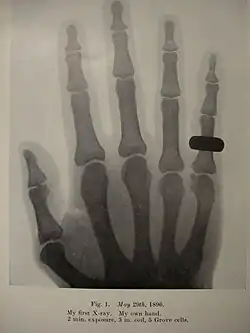

First X-ray taken by Holland, of his own hand. (Liverpool, 1896)

He started research on radiology in 1896, after reading about Wilhelm Röntgen's experiments in this field. Thanks to his meticulous work and advancements in his technique, Holland was able to produce radiographs that were far in advance for many years, compared to the standard practice.[3] Along with such names as Heinrich Albers-Schönberg (Germany), Antoine Béclère (France), Etienne Henrard (Belgium), Guido Holzknecht and Robert Kienböck (Austria), Thurstan Holland is considered one of the pioneers in Europe.[5]